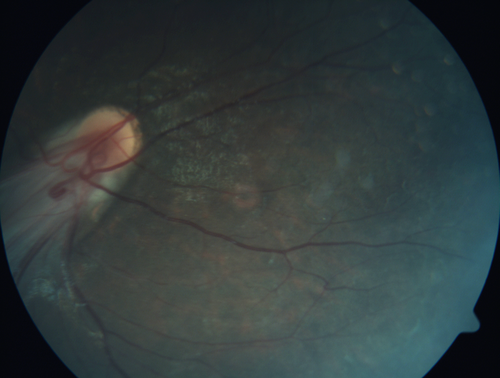

Familial Exudative Vitreoretinopathy - FEVR - Stage 4b OD

10 year old child with poor vision OD from birth.  The left eye had vascular remodelling in the temporal periphery with preretinal abnormalitlies seen on OCT.  The patient never returned for a fluorescein angiogram.  Left eye is either stage 1 or stage 2. no family history